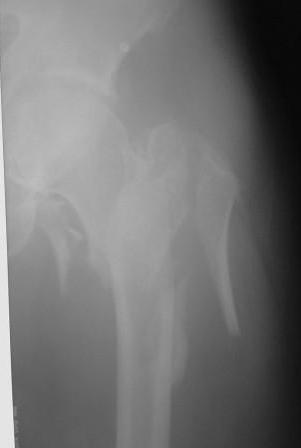

Здесь 83 года, травма в результате падения

Djoldas Kuldjanov, M.D.

Department of Orthopedic Surgery

St. Louis University